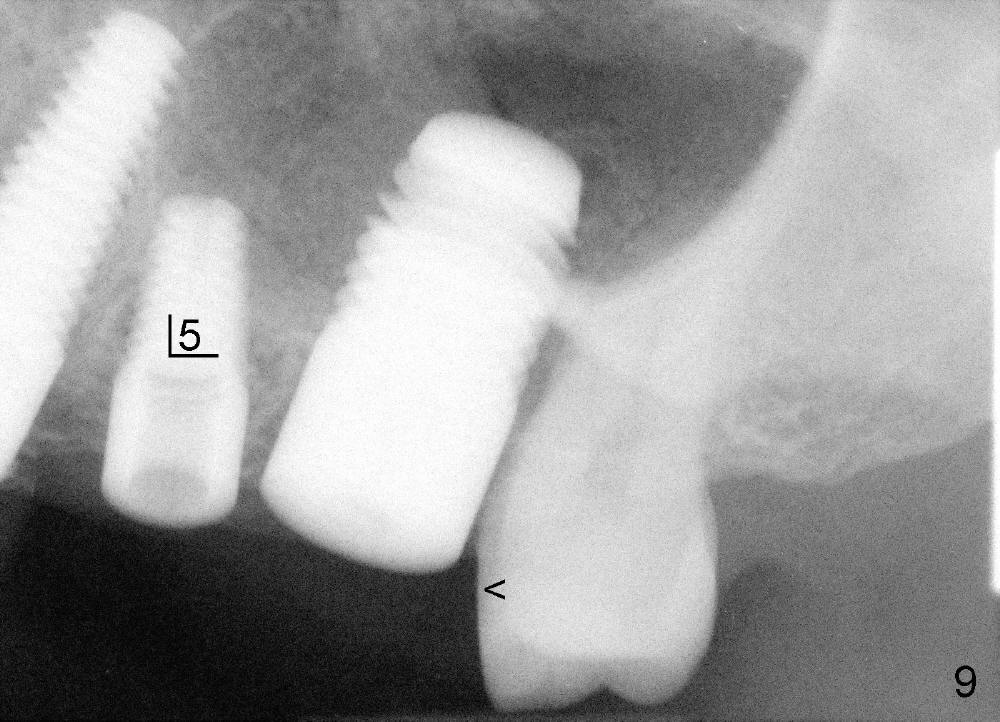

A 47-year-old lady has lost an upper left bridge (Fig.4,7). She is a dental phobic, but is concerned about cosmetics. Immediate implant and immediate provisional for the 1st bicuspid are easily accepted. There is a sinus septum above. Intraop PAs show that 4.5x17 mm tap (Fig.5) and 5x17 mm implant (Fig.6, insertion torque > 60 Ncm) are placed mesial to the septum without sinus membrane perforation. An abutment is placed immediately and an immediate provisional is fabricated.